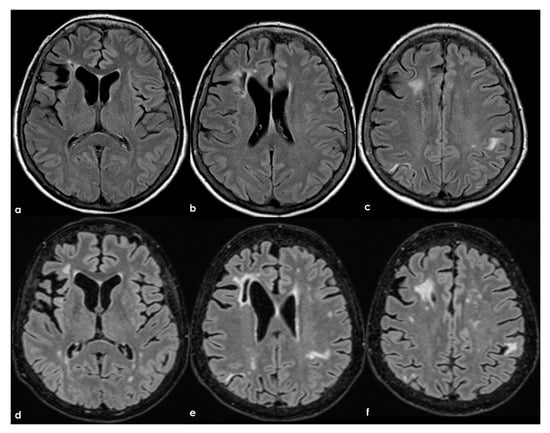

Figure 6.

Brain MRI (axial FLAIR in panels (a–c) and the corresponding DWI slices in panels (d–f)) showing multifocal ischemic lesions in the left PCA territory with a patent PCA on MRA (panel (g)).

A different situation is illustrated in Figure 7, where the multiple ischemic lesions are in different vascular territories.

Figure 7.

Brain MRI (axial FLAIR in panels (a,b) and coronal T2W sequence in panels (c,d)) showing multiple cortico-subcortical ischemic lesions on both hemispheres and only few mildest SVD markers.

In the longitudinal evolution of neuroradiological patterns, SVD markers might appear, as in Figure 8 (same patient as in Figure 7 but 8 years later and without new clinical events on anticoagulant treatment).

Figure 8.

Brain MRI (axial FLAIR) at baseline (panels (a–c)) and after 8 years (panels (d-f)), showing the increase of WMHs in the subcortical white matter.